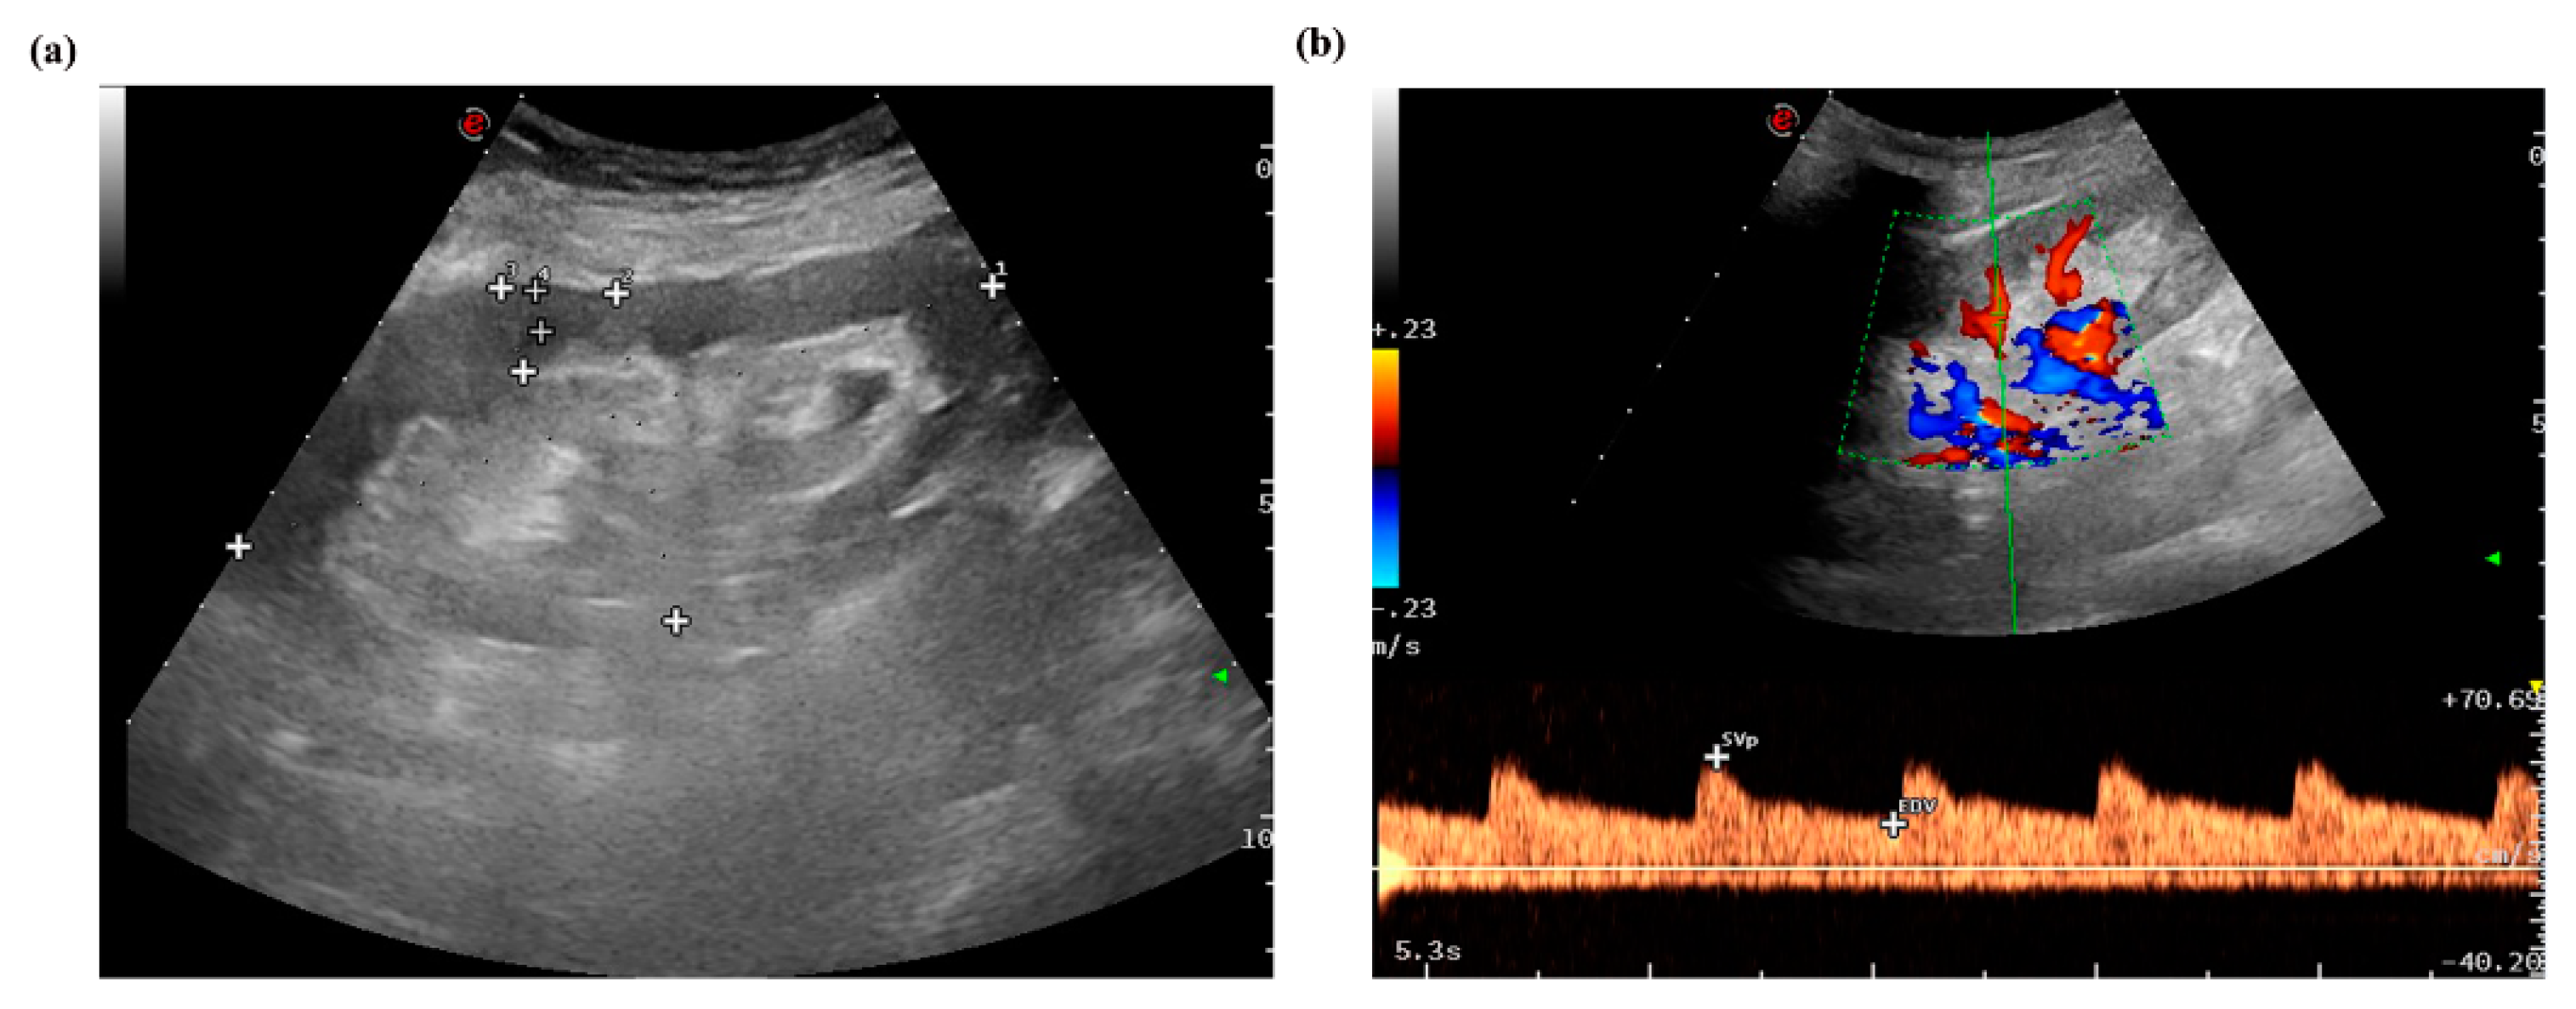

Figure 2. (a) B-mode image, measurement of renal size including renal length, width, and renal parenchyma thickness. The plus signs mean activating the measurement key after freezing the ultrasound imagine and the green color means focal position.(b) CDFI image, measurement of resistive index (RI).

The patients were evaluated with B-mode imaging, Doppler ultrasound and p-SWE measurements 1 week before biopsy. The measurement procedure was performed by using the software Esaote(version MyLab 8Exp, Genova, Italy), and a convex broadband probe (C1–8). All measurements were obtained by an ultrasound sonographer (Y.G) who was blinded to biopsy results. The sonographer has more than 10 years of ultrasound experience and more than 200 shear wave elastography examinations. The size of the transplanted kidney (length and width) and skin-allograft distance were measured by B-mode imaging (Figure 2a). CDFI was used to evaluate blood perfusion of the transplanted renal, such as resistance index (RI) (Figure 2b).